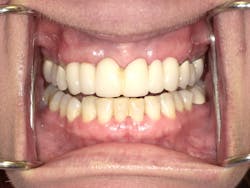

Pretreatment anterior view; maxillary bridge Nos. 3–14 with a pontic span Nos. 6–11

Karen returned, and under conscious sedation the dentist removed the existing bridge and placed implants as planned. An interim temporary bridge was constructed to get her through the healing process and until abutments would be placed. In the meantime, individual crowns were completed on Nos. 3, 4, and 5. Shortly thereafter, crowns were completed on the left side on teeth Nos. 12, 13, and 14. She is currently awaiting the final implant supported bridge on Nos. 6–8 and 9-11.